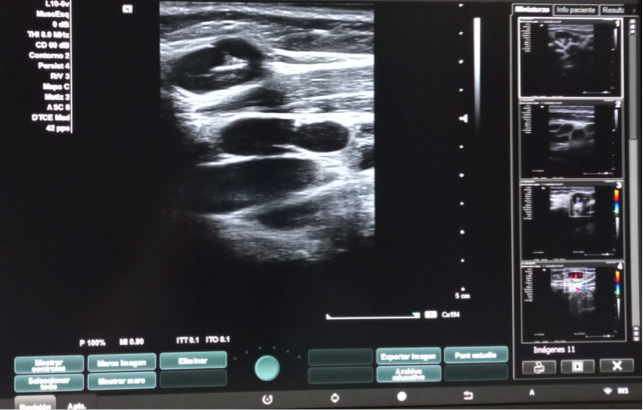

Hallazgos ecográficos

Dos adenopatías en territorio laterocervical derecho, con hilio central y doppler positivo, alguna con diámetro transversal superior al longitudinal, de probable origen reactivo y una adenopatía supraclavicular sin hilio central y con vascularización generalizada.

A las dos semanas de iniciar el tratamiento con ibuprofeno, se realiza el control ecográfico que evidencia ganglios cervicales bilaterales, inespecíficos de probable carácter reactivo y menores de 10 mm en el eje corto, por lo que finalmente se decide no exéresis de adenopatía.